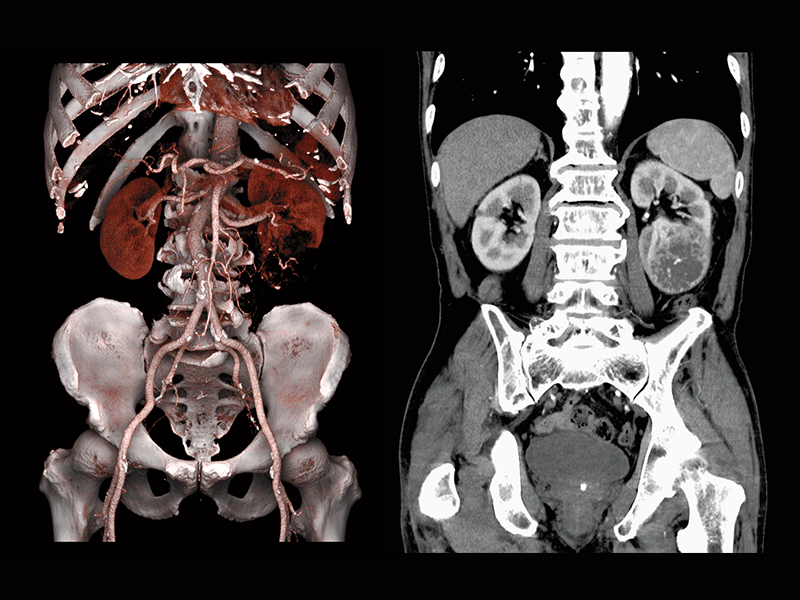

Renal cell carcinoma(80 kV)

Abdominal aortic occlusion